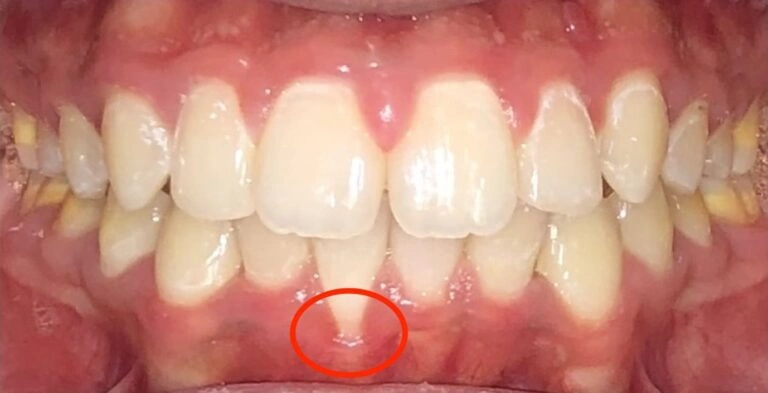

Visual Example:

Patient Example (young child)